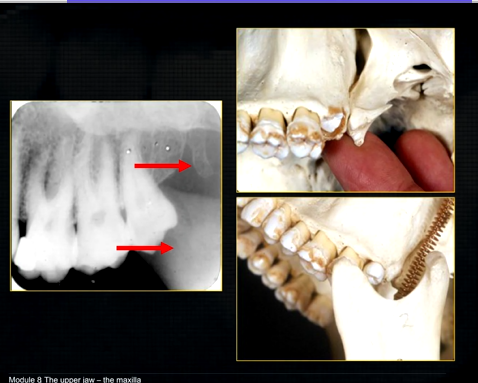

1st image taken using the bisected angle technique

2nd was taken using the geometrically accurate, paralleling technique

upper image is geometrically distorted

shadow caused by zygoma

this was taken using the bisected angle technique

x ray beam was directed below the zygoma

very lower of the zygoma is seen - projected above the apices

pterygoid hammulus - supports the muscles of the soft palate

coronoid process of the mandible